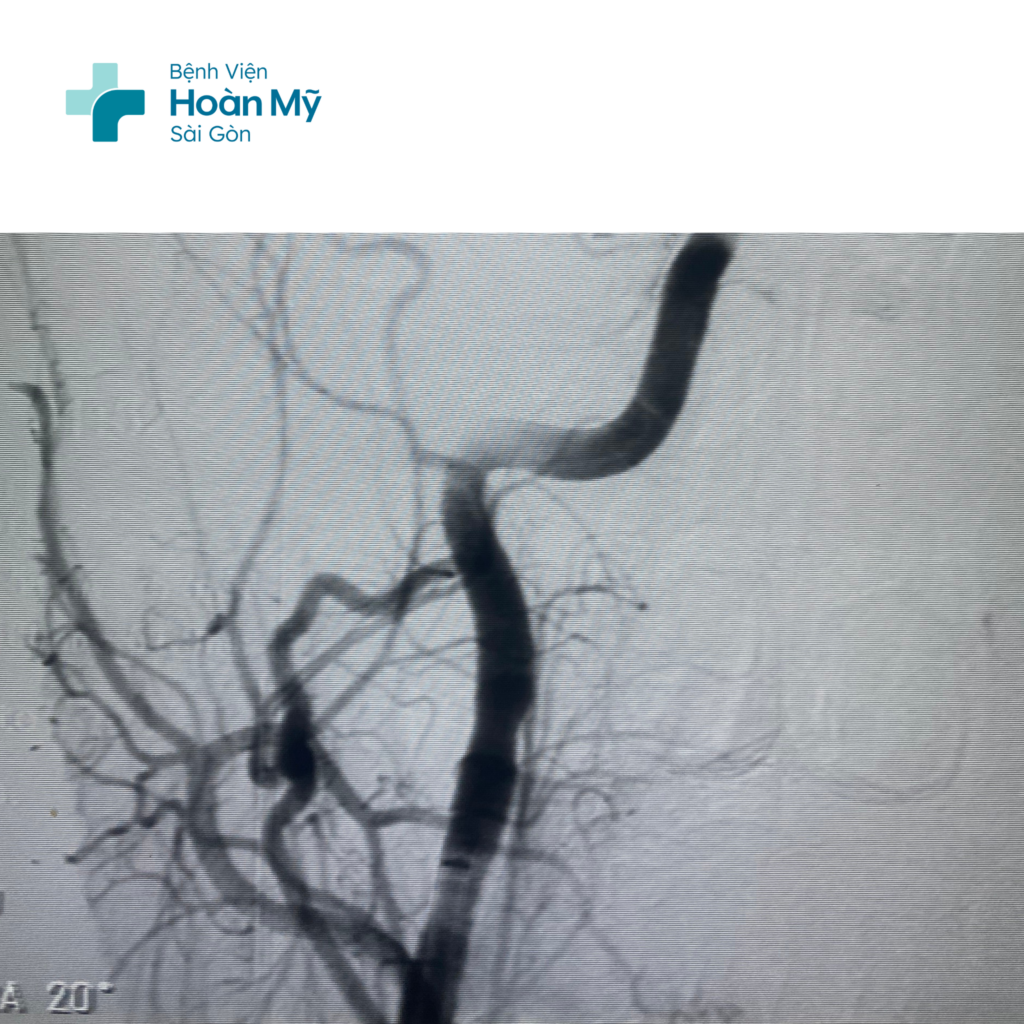

Hình ảnh ĐM cảnh trong và não giữa phải trước (trái) và sau khi can thiệp (phải)

Tại đây, các bác sĩ tiến hành dùng dụng cụ chuyên biệt để đưa lên động mạch não, lấy cục máu đông đang làm tắc mạch máu của người bệnh. Khoảng 30 phút sau khi can thiệp, tình trạng người bệnh cải thiện, chân tay đã cử động được.